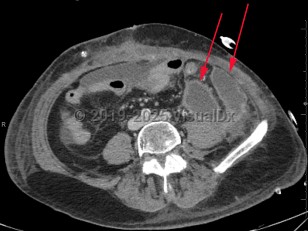

Intraabdominal abscess

A collection of pus located inside the abdominal cavity that forms as a result of inoculation of one or more pathogens into a normally sterile intraabdominal location.

The clinical presentation is varied and depends on the location of the abscess in the intraabdominal cavity. Vague abdominal discomfort is common, and pain may localize to a site of intraabdominal inflammation (in the patient with diverticulitis, for example). Fever and leukocytosis are also seen. The clinician should be mindful that patients who are immunosuppressed may have very mild and nonspecific symptoms. Patients who have a spinal cord injury or altered mental status may be similarly difficult to diagnose.